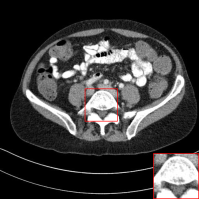

D.1 Low-Dose CT

In this subsection, we show the additional qualitative results on Low-Dose CT dataset authorized by Mayo Clinic [Moen etย al.(2021)Moen, Chen, Holmesย III, Duan, Yu, Yu, Leng, Fletcher, and McCollough] in Figure 13. As shown in Figure 13, previous methods tend to lose details and generate blurred results. However, our method removes the noise, while preserving the details of organs. It shows that our method is also practical for medical image denoising.

Figure 13: Qualitative results of our method and other baselines on Mayo Clinic Low Dose CT dataset. As shown in the highlighted red box, the reconstructed images by our method have few noise and preserve the details of organs. The display window is [160,240]160240[160,240] HU.